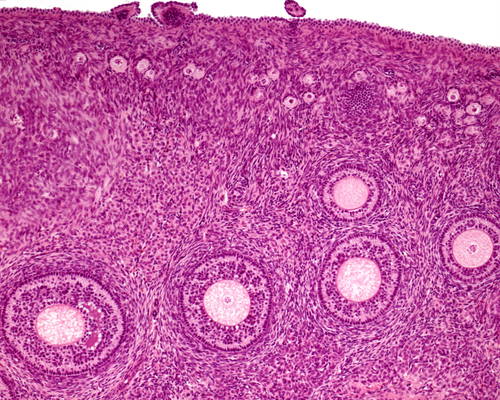

Ovarian tissue freezing can be an alternative method to promote fertility, especially in women who cannot undergo egg freezing due to cancer or other medical reasons, researchers say.

The procedure which is still considered experimental involves removal and freezing of ovarian tissue for later use.The study, published in the journal Reproductive Sciences, showed that ovarian tissue freezing helped nearly four out of 10 (37.7 per cent) women to have children later in life. Between 1999 and 2016, a total of 309 ovarian tissue freezing procedures resulted in 84 births and eight pregnancies that lasted beyond the first trimester, data showed."Despite the clinical progress within the past two decades, the procedure still remains in the experimental realm," said Fernanda Pacheco from the Innovation Fertility Preservation and IVF in New York, US.

"Now, women considering this procedure to preserve fertility and postpone childbearing have more information at their disposal. Given these recent data, ovarian tissue cryopreservation should be considered as a viable option for fertility preservation," Pacheco added.The procedure also restored reproductive functions. It reversed menopause in nearly two out of three women (63.9 per cent). This included either a resumed menstrual cycle, ovarian follicular growth, or natural fertility.Ideally, egg freezing is done by cancer patients before beginning their treatments such as chemotherapy, radiation therapy, which can have lasting impact on their fertility.

Kutluk Oktay, from New York Medical College, who performed the world's first ovarian tissue cryopreservation in 1999 considers the procedure is superior to egg freezing as it can also reverse reproductive functions."The next frontier is to explore the procedure's potential in delaying childbearing among healthy women, not just cancer patients," Oktay added.